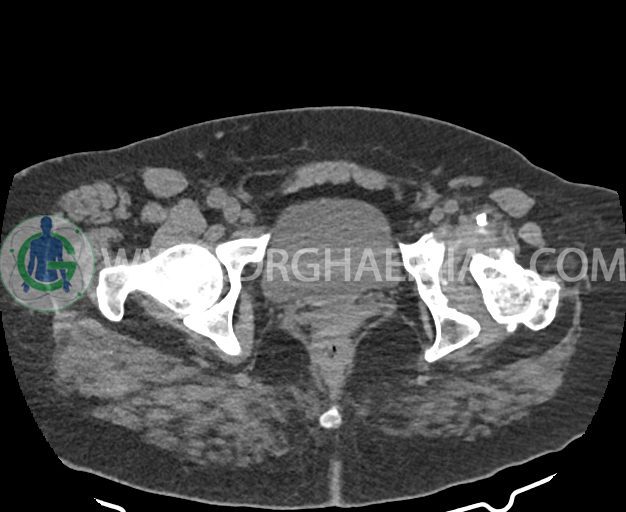

در سی تی اسکن اسپیرال شکم و لگن بدون کنتراست (مولتی دیدکتور 16 با مقاطع ظریف و بازسازی های ساژیتال و کرونال) :

شواهد استئوآرتریت ثانویه به صورت remodeling اسکلروز و کیست های ساب کندرال و کاهش فاصله مفصلی در کمپارتمان لترال hip چپ همراه با دفورمیتی استابولوم و خصوصا سر فمور و flattening آن دیده می شود.